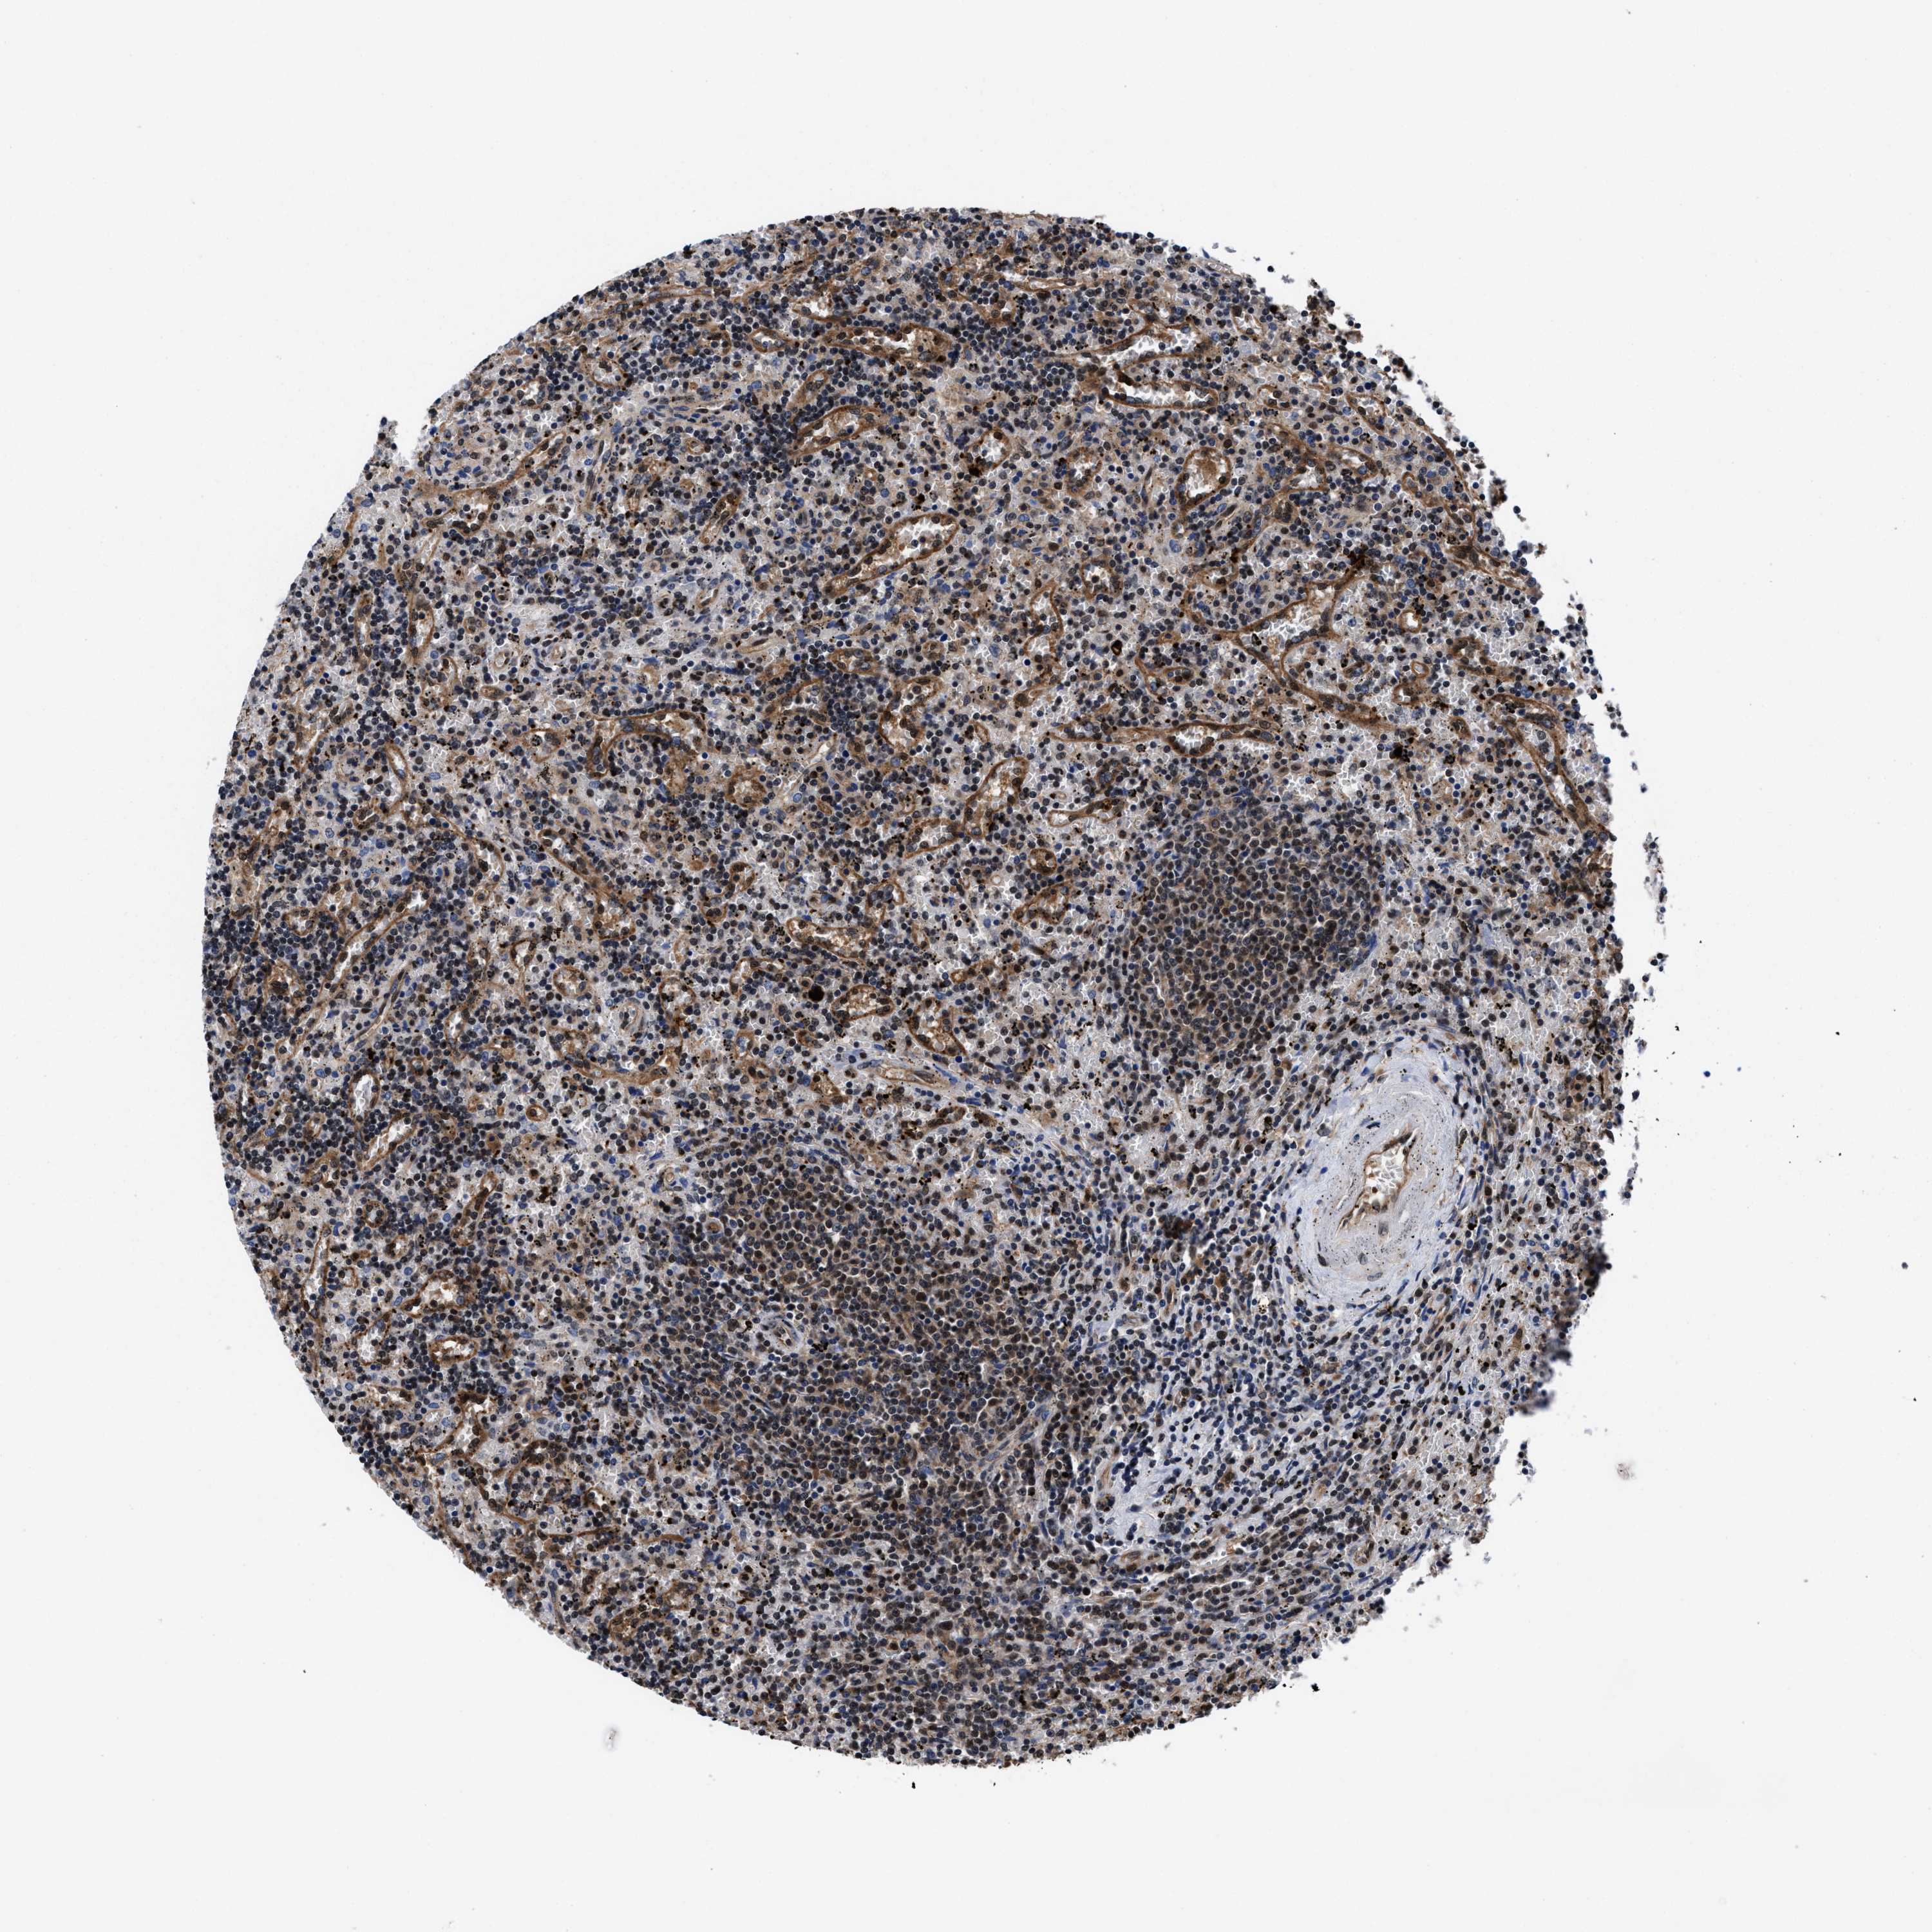

CANCER LYMPHOMA Show tissue menu

LYMPHOMA - Protein expressioni

A mouse-over function shows sample information and annotation data. Click on an image to view it in a full screen mode. Samples can be filtered based on level of antibody staining by selecting one or several of the following categories: high, medium, low and not detected. The assay and annotation is described here.

Antibody stainingi

Antibody staining in the annotated cell types in the current human tissue is reported as not detected, low, medium, or high, based on conventional immunohistochemistry profiling in selected tissues. This score is based on the combination of the staining intensity and fraction of stained cells.

Each image is clickable and will lead to virtual microscopy that enables deeper exploration of all samples and also displays staining intensity scores, fraction scores and subcellular localization as well as patient and tissue information for each sample.

HPA022434

Staining

High

Intensity

Strong

Quantity

>75%

Location

Nuclear

Hodgkin's disease, NOS

Malignant lymphoma, non-Hodgkin's type, High grade

Malignant lymphoma, non-Hodgkin's type, Low grade